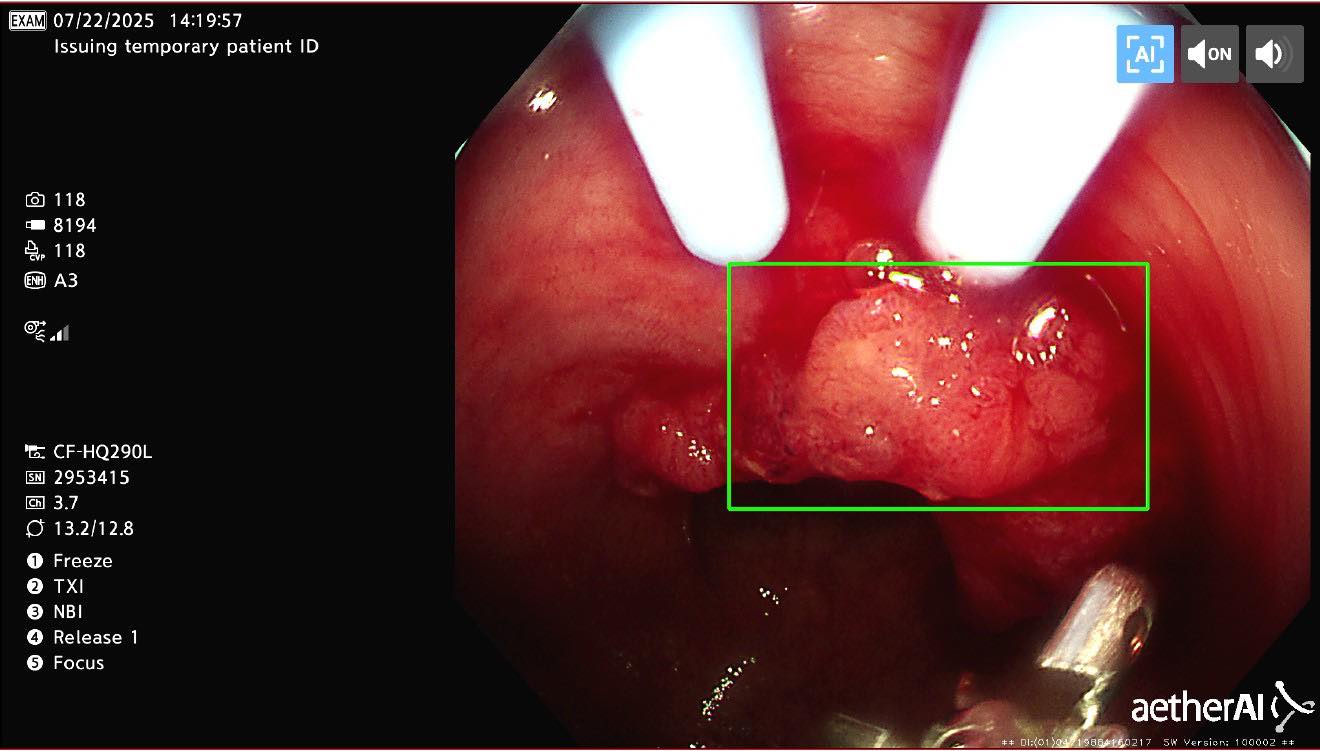

很多人覺得大腸癌是五、六十歲以後才會遇到的事,但近幾年,年輕患者越來越多。更可怕的是,早期幾乎沒有明顯症狀,有時只是偶爾大便帶血、排便習慣改變,或體重悄悄下降,就被當作痔瘡、腸胃炎拖了好幾個月。

一次大腸鏡檢查,也許就能改變整個人生。

我身為醫師,真的不希望再看到有人因為「覺得還年輕」而錯過了治療的黃金時間。你不一定要害怕,但請你一定要重視。

健康檢查,不是等出事才做,更不是為了嚇自己,而是給自己一個未來還能放心生活的機會。